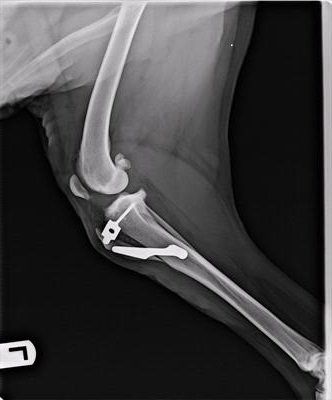

TTA (tibial tuberosity advancement) - this is now being performed at Penrith Veterinary Hospital. Special implants are used in the bone below the knee to change the effective angle of the joint. Even though it is a much more complex procedure that ligament replacement, most dogs are walking reasonably within 5-7 days of the procedure, so recovery is faster.